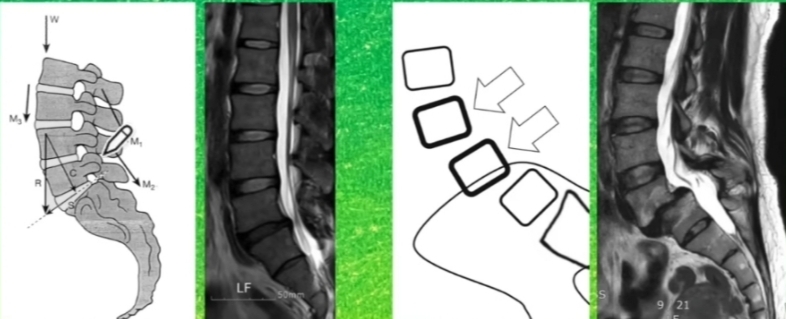

하나의 척추가 인접하는 밑의 척추에 비해 정상적인 정렬을 이루지 못하고 앞으로 빠져있는 상태.

흔히 요추를 제자리로 돌리기 위해 척추 굴곡의 동작을 시키게 되는데 척추의 신전 자세에서 척추의 안정성이 더 높아지는 것을 볼 수 있다.